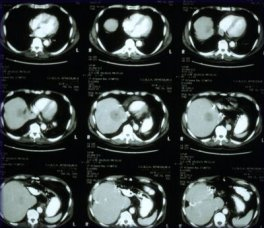

RF energy is fed to the tumor through a very small needle with an electrode on the tip. The needle is inserted into the tumor under imaging guidance, such as CT scan or ultra- sound. The electrode generates heat up to 100 degrees Celsius. After 10 to 12 minutes of continuous contact with the tumor tissue, the RF energy “cooks” a l-inch to 2-inch sphere, killing the tumor cells. Larger tumors can be treated by cooking overlapping spheres.

Early results from a multicenter study that included the Clinical Center look promising: of 21 kidney tumors treated, 14 (67 percent) were no longer visible on x-ray five months after RF treatment. One patient remains cancer-free 18 months after treatment. For kidney tumors 3 centimeters or less, 1 1 of 14 (79 percent) showed no activity on follow-up.